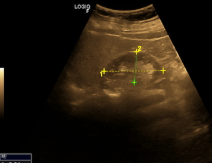

Autosomal Dominant Polycystic Kidney Disease (ADPKD)

More common than ARPKD. Bilateral renal enlargement due to formation of many cysts of various sizes. The cysts gradually enlarge as the patient ages. Over time cysts will compress and destroy normal tissue.

ADPKD indications

Chronic UTI’s, Stone Formation, Back Pain, Headache, Increasing Abdomen Size, High blood pressure, Renal Insufficiency. (50% diagnosed with renal hypertension)(50% will need dialysis or transplant due to renal failure). Increased Bun & Creatinine, Decreased GFR

Radiological Images description ADPKD

Cysts may also be present in the liver, pancreas, and/or spleen. Multiple cysts noted.

ADPKD image